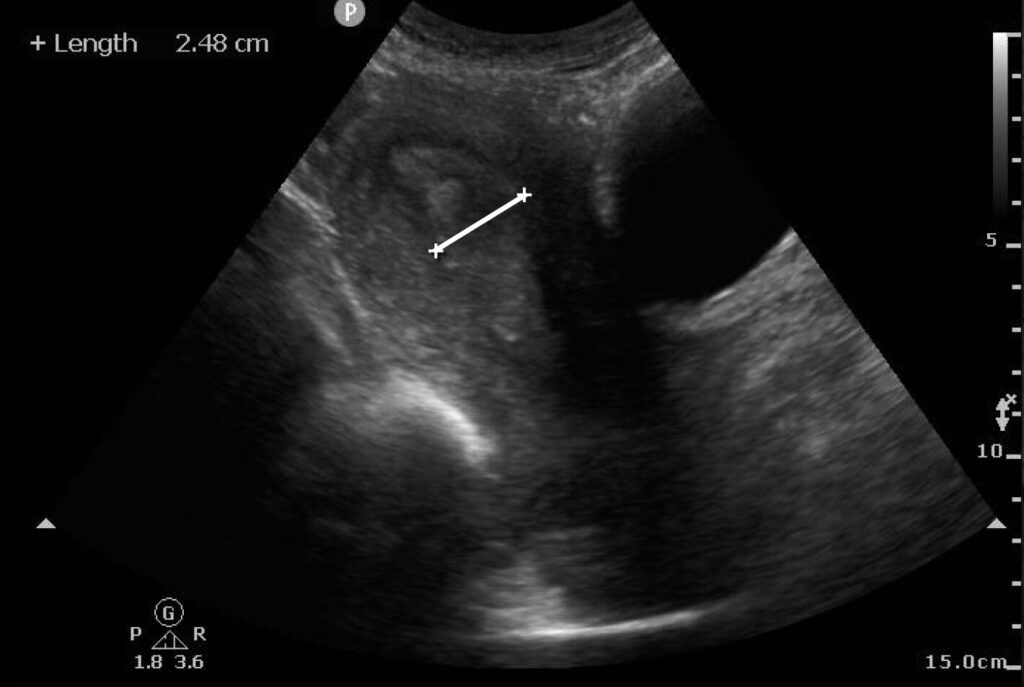

POCUS for identification of RPOC starts with visualization of the uterus and endometrial stripe, using the bladder and vaginal stripe as landmarks (Image 1) (Video 1). To perform the scan, place the probe in the sagittal plane superior to the pubic brim. The normal uterus appears homogeneous and isoechoic or hyperechoic. The endometrium is located centrally within the uterus and appears more hyperechoic. Fanning the probe can help identify the endometrium, which then can be measured within the uterus in the sagittal plane, at the thickest area of echogenicity, without the inclusion of fluid or myometrium (Image 2) if there is concern for RPOC.

Image 2: Measured endometrium that appears thickened and heterogeneous